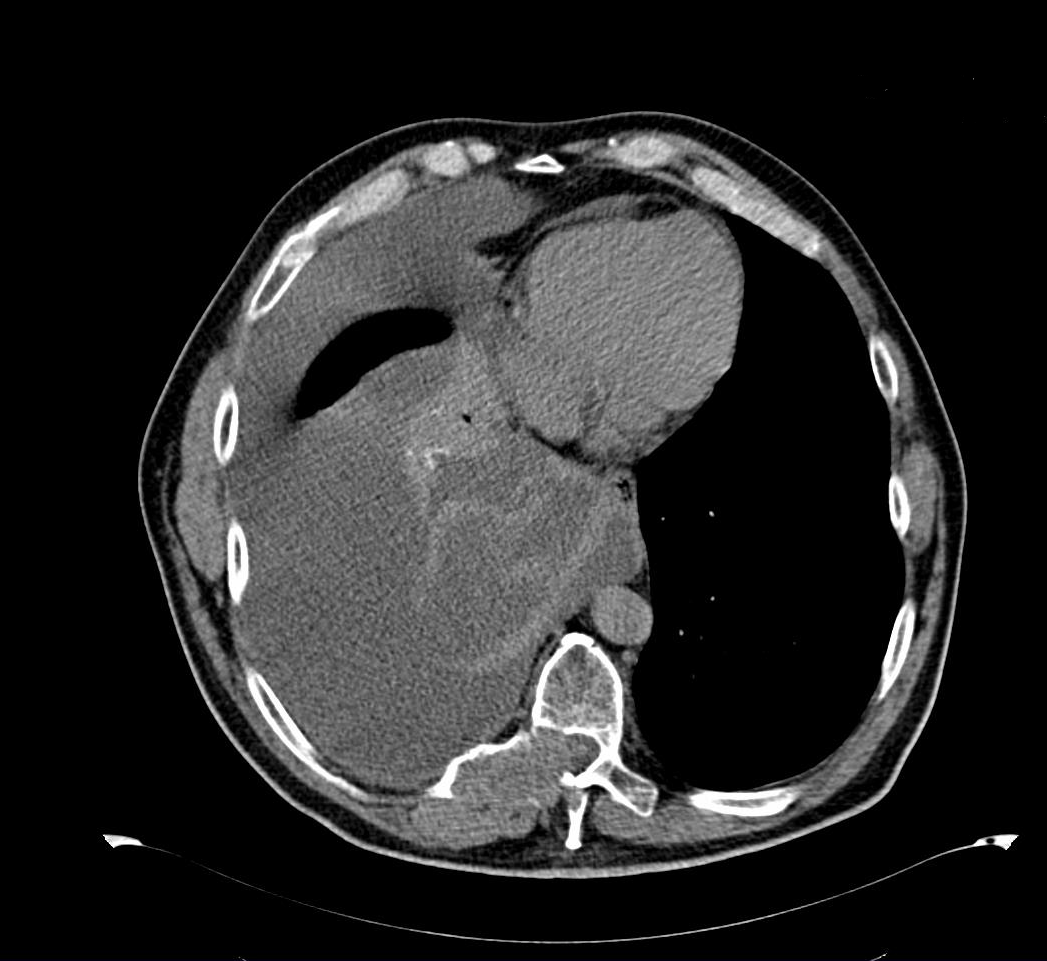

Importante colección anecoica supradiafragmática compatible con derrame pleural masivo (2/3 pulmón derecho), con flóculos ecogénicos (tongue-like sign) sugerentes de parénquima pulmonar atelectásico. Escasa colección anecoica pericárdica. Se identifica en riñón izquierdo una imagen heterogénea de bordes bien definidos en polo superior invadiendo pelvis, de unos 52x58x60 mm, con aumento de captación doppler.Pruebas complementarias

Ante sospecha de carcinoma renal con derrame pleural paraneoplásico remitimos a urgencias para ingreso y estudio. En 48 horas se llega al diagnostico final de carcinoma de células claras renal estadio IV con afectación pulmonar, pleural, ganglionar y ósea grupo pronóstico intermedio.Tratamiento y planes de actuación